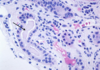

Wilms tumor Microscopic features (3)

- Triphasic pattern*

- Primitive blastema (small/dark undifferentiated cells)

- Epithelial component (abortive tubules/glomeruli)

- Stroma (Fibrous or myxoid patterns; may contain mesenchymal elements (cartilage, muscle, bone)

Wilms tumor microscopic features (3):

Triphasic pattern

- Primitive blastema (small/dark undifferentiated cells)

- Epithelial component (abortive tubules/glomeruli)

- Stroma (Fibrous or myxoid patterns; may contain mesenchymal elements (cartilage, muscle, bone)